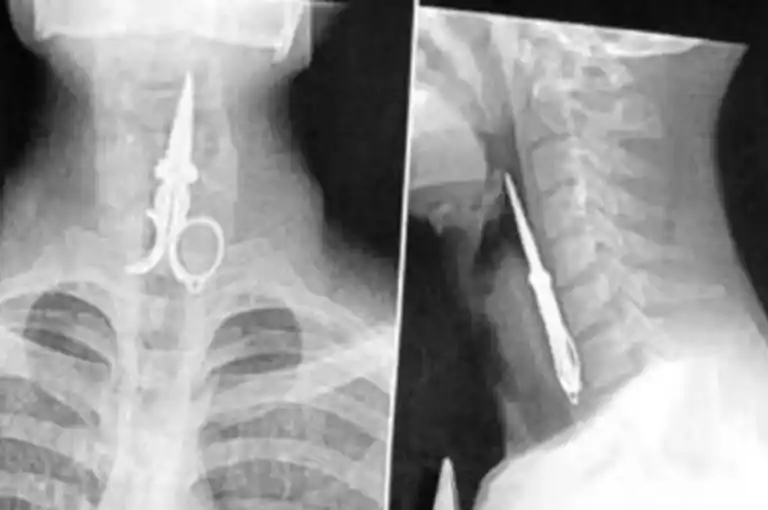

El convicto Axel Hernán Rojas ingirió la mitad de una tijera, poniendo en evidencia la crisis de salud mental en el sistema penitenciario.

En esta ocasión, tras ingerir el objeto metálico, fue trasladado al hospital donde, aunque se negó a recibir atención, los médicos determinaron que no requería cirugía y pudo expulsar la tijera por sus propios medios. Actualmente, se encuentra fuera de peligro y ha regresado al penal.